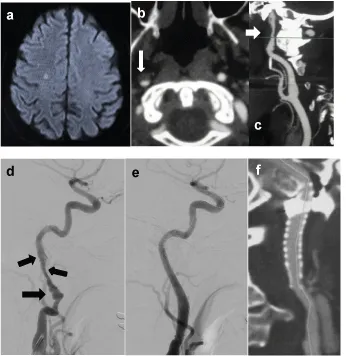

Aiming the evaluation of the CASPER-RX stent use in different pathologies of the extra cranial internal carotid artery, patients with atheromatous disease with stenosis between > 70% and > 90%, and all with ischemic symptoms even the use of antiplatelet drugs, were previously evaluated with ultrasound, angio MRI or angio tomography and lesions confirmed by angiography. As patients with acute and sub-acute disease with spontaneous and sub occlusive iatrogenic dissection and pseudo aneurysms, also with ischemic symptoms. Histories of brief cases and radiographic images in a case of severe and symptomatic stenosis > 90%, symptomatic sub occlusive dissection and sintomatic pseudo aneurysm associated with dissecting shown in Figures 1 (a,b,c,d,e and f), 2(a,b,c,d,e and f) and 3(a,b,c,d and e) respectively.

The procedure was performed under local anesthesia with sedation or general anesthesia. All patients had previous use of dual antiplatelet therapy with clopidogrel 75mg/day and aspirin 200mg/day. In 05 of the cases (in sub occlusive atheromatous disease with stenosis between >80 and ≥90% required pre coronary balloon dilation (cases nº3, nº11, nº12, nº19 and nº29) (Table 1) (Figure 1c). It was used cerebral protection system in all cases of atheromatous disease, in cases of dissection and pseudo aneurysm, only micro-guide 0.014 was used. In one dissection case (case nº7) where there was the presence of free intraluminal clot, it is used a cerebral protection system. All patients received 5,000 units of heparin during the procedure and atropine (0.5 mg) prior to stent implantation. Patients continued with dual antiplatelet therapy after the procedure.

All the stents, a total of 53 and different measures [7×30(12), 7×40(1), 8×25(4), 8×30(12), 8×40(21), 9×30(3)] (Table 1), were satisfactorily implanted, without any difficulties with the navigation and delivery systems, even with the use of telescoped stents. The rate of complications was 4%, a case with a small area dissected of just detachment to the amount of stent, without clinical manifestations and it was opted to put a second telescoped stent to avoid the risk of dissection (case nº9) and femoral hematoma in another case. In two other cases, the use of more than one stent was necessary, in a telescoped way, due to the presence of multiple lesions. Two pseudo aneurysms (case nº8), and a pseudo aneurysm associated with extensive dissection (case nº13) (Figure 3 (a,b,c,d and e)), there were no difficulties to navigate to the implant system through the first implanted stent, as well as the release of a second stent telescoped smoothly. All the patients had a favorable clinical evolution, no thromboembolic event at the clinical and imaging (ultrasound and/or angiography carotid tomography) follow-up that showed patency of the stents in all cases, as well as the absence of re-stenosis, occlusion of pseudo aneurysms and complete recanalization in cases of dissection.